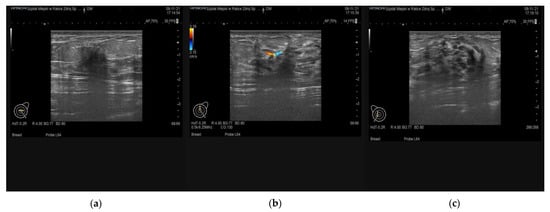

6. Imaging Findings